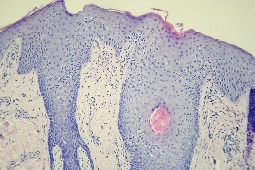

Legenda do ryciny:

Ryc. 1 Histologiczne cechy przyłuszczycy plackowatej wielkoogniskowej przechodzącej w ziarniniaka grzybiastego rozwiniętej u młodego mężczyzny ze śluzówkowodominującą odmianą pęcherzycy zwykłej w wywiadzie, która to pęcherzyca była leczona masywnie immunosupresyjnie, także cyklofosfamidem doustnie, z uzyskaniem remisji kliniczno-laboratoryjnej